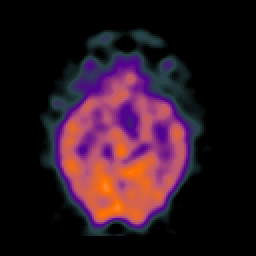

SPECT TC Study #6 -- Slice #22

[Home][Help][Clinical][Tour 1][Tour 2][Tour 3] Slice 22